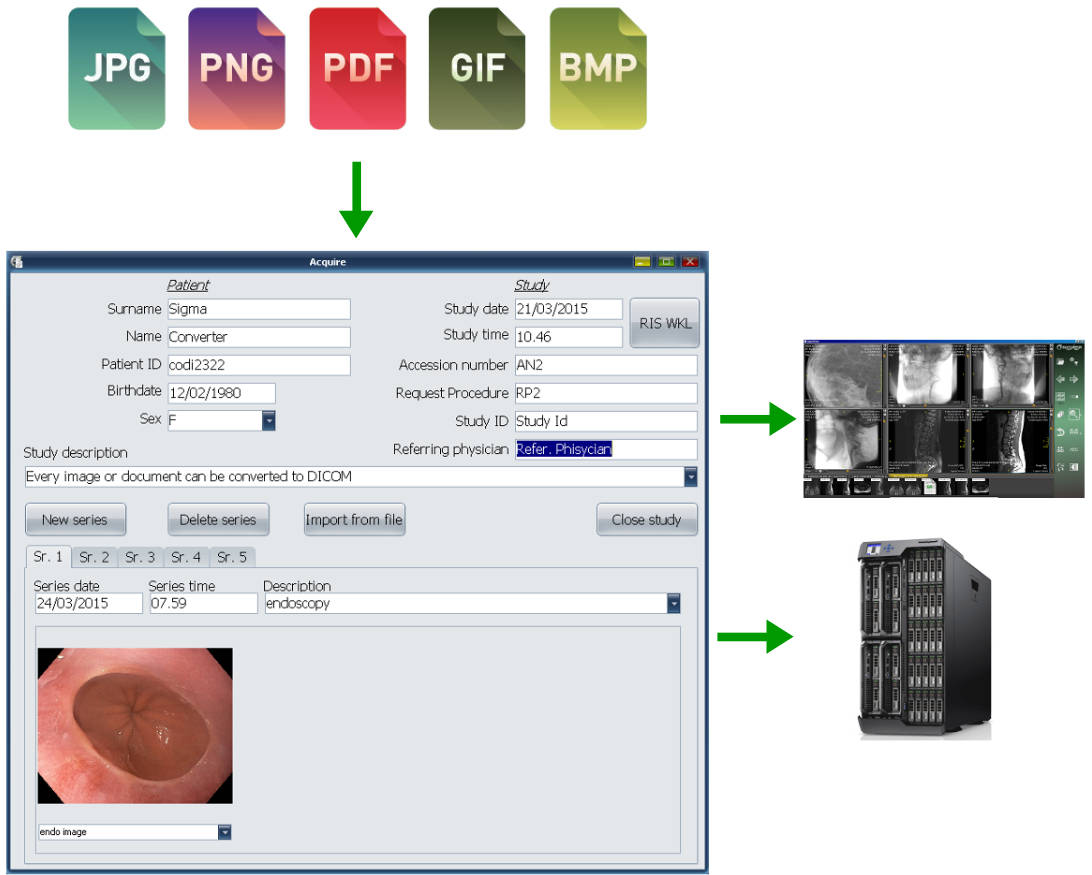

Лазерная камера сетевая для печати изображений на пленке стандарт dicom